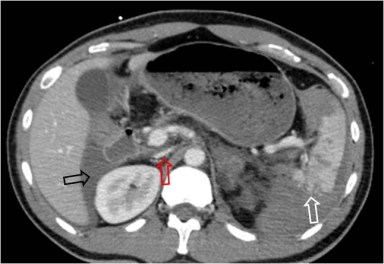

SIGNO DEL CALCIO TANGENCIAL

Consiste en el desplazamiento del calcio de la pared aórtica, que se sitúa por fuera de la esperada circunferencia del aneurisma. En ocasiones, en aortas muy calcificadas, puede verse también una interrupción del anillo calcificado, con los márgenes abiertos, asimismo apuntando hacia fuera de la circunferencia. Corresponde a un punto de debilidad de la pared y suele ser el sitio de rotura.

Se trata, pues, de otro signo de rotura contenida o inminente. La imagen es del mismo paciente del signo anterior, ésta en fase portal. Obsérverse como los calcios intimales (flechas) están desplazados.

SIGNO DE LA AORTA CAÍDA o SIGNO DEL ABRAZO AÓRTICO

Se trata de otro signo de rotura contenida o inminente. Corresponde a una debilidad de la pared aórtica que provoca que la cara posterior de ésta aparezca como caída sobre el cuerpo vertebral (y ambos psoas, como en este caso -flechas rojas-). También se considera el signo presente cuando es visible un área en la que la pared posterior de la aorta no es identificable como una línea definida.